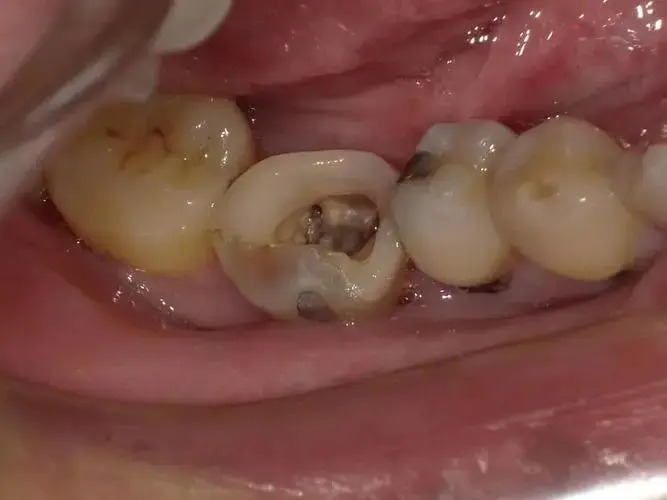

残留的牙冠,可不可以不拔?

很多人牙齿出现残冠问题的时候,想着能不拔就不拔。事实上,残冠在临床上有两种方式,一种是保留使用,另一种方式就是要拔除。

如果你的残冠是健康的,那么还有保留的必要,但如果已经不健康,一定要拔掉,因为看起来不起眼的残冠,会给人的健康带来较为严重的问题。

残冠不拔对牙齿的影响

1、牙齿是空心结构,牙齿大面积龋坏后,导致牙髓腔根管暴露在口腔中,由于口腔   环境有细菌,细菌可以通过根管直接到达根尖部外面的颌骨中,形成根尖周围的慢   性炎症。病灶牙的细菌及其产生的毒素,通过血液循环到达全身各个器官,导致各   个部位的病变;

2、残冠的尖锐边缘长期刺激口腔黏膜,可能会导致口腔癌的发生;

3、残冠具有较强的引菌作用,成为细菌滋生、繁殖的部位,导致长期慢性疼痛、牙龈出血、松动、咀嚼无力,严重时牙周炎从病灶牙处,蔓延到邻近牙齿,可导致邻近牙齿的松动;

4、残冠容易储藏软垢,不容易清洁,细菌滋生以后可引起口臭,给患者的社交活动带来不便;

5、如果是恒牙残冠,比如上颌后牙,靠近上颌窦,病变穿通窦腔底可引起头痛、鼻塞,引起上颌窦炎症;

6、如果是乳牙残冠,可导致恒牙萌出受到障碍,萌出过早或过晚,导致牙列不齐,后期矫正给患者带来较大的经济负担。

所以,对于残冠是保留还是拔除,需要去听专业医生的,一定要尽早进行处理,如果能保留可做完根管治疗 、打桩再做冠,让其尽快恢复到正常使用状态。